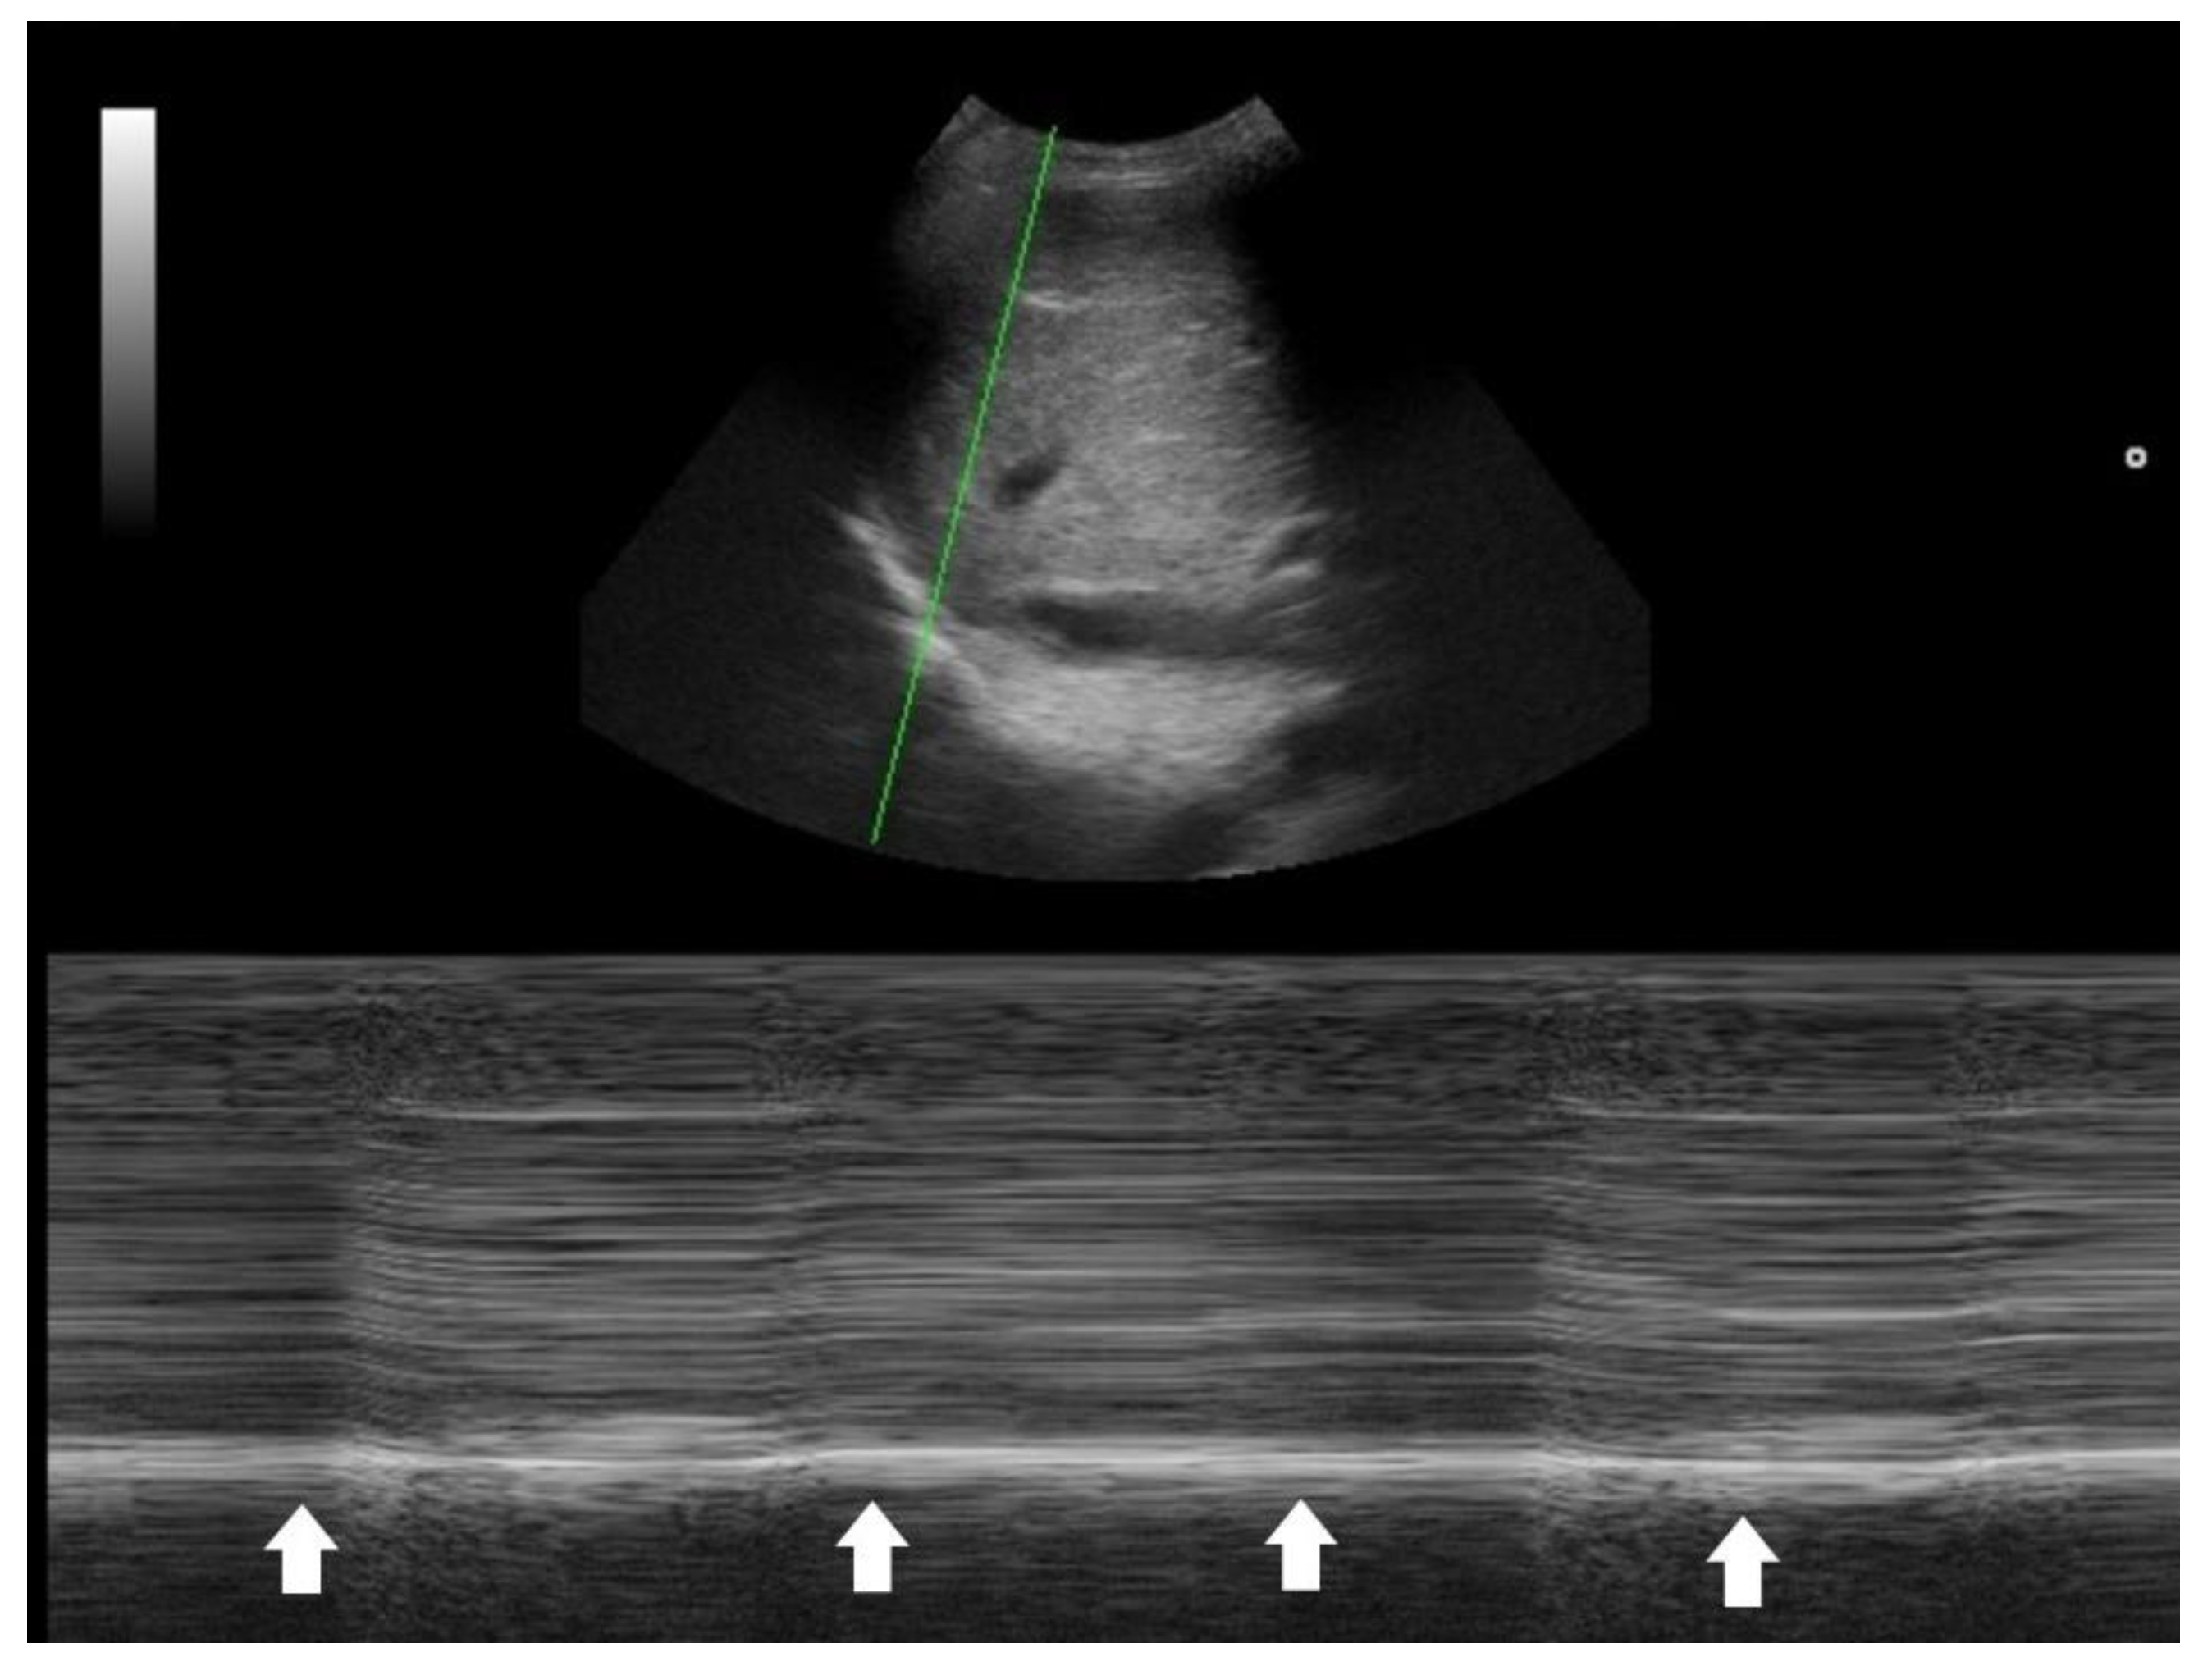

One key clinical implication of PSI and CURB-65 is the prognostic value of co-morbidities, physical signs, and laboratory data in CAP. PoCUS serves as a powerful tool to detect occult co-morbidities—such as heart failure, chronic kidney disease, and liver disease—that are incorporated into the PSI score [32]. Laboratory items in PSI and CURB-65 aim to identify signs of sepsis. In this context, PoCUS can help confirm a hyperdynamic left ventricle in patients with tachycardia and/or hypotension [40,41,42], or a hyperdynamic diaphragm in tachypneic patients as a compensatory response [43,44]. Suboptimal diaphragmatic excursion in a patient is an ominous sign, indicating poor respiratory endurance and limited reserve (Figure 4) [45,46,47,48].

Figure 4. M-mode tracing of diaphragm showed minimal respiratory excursion (arrows), indicating a poor diaphragm function.